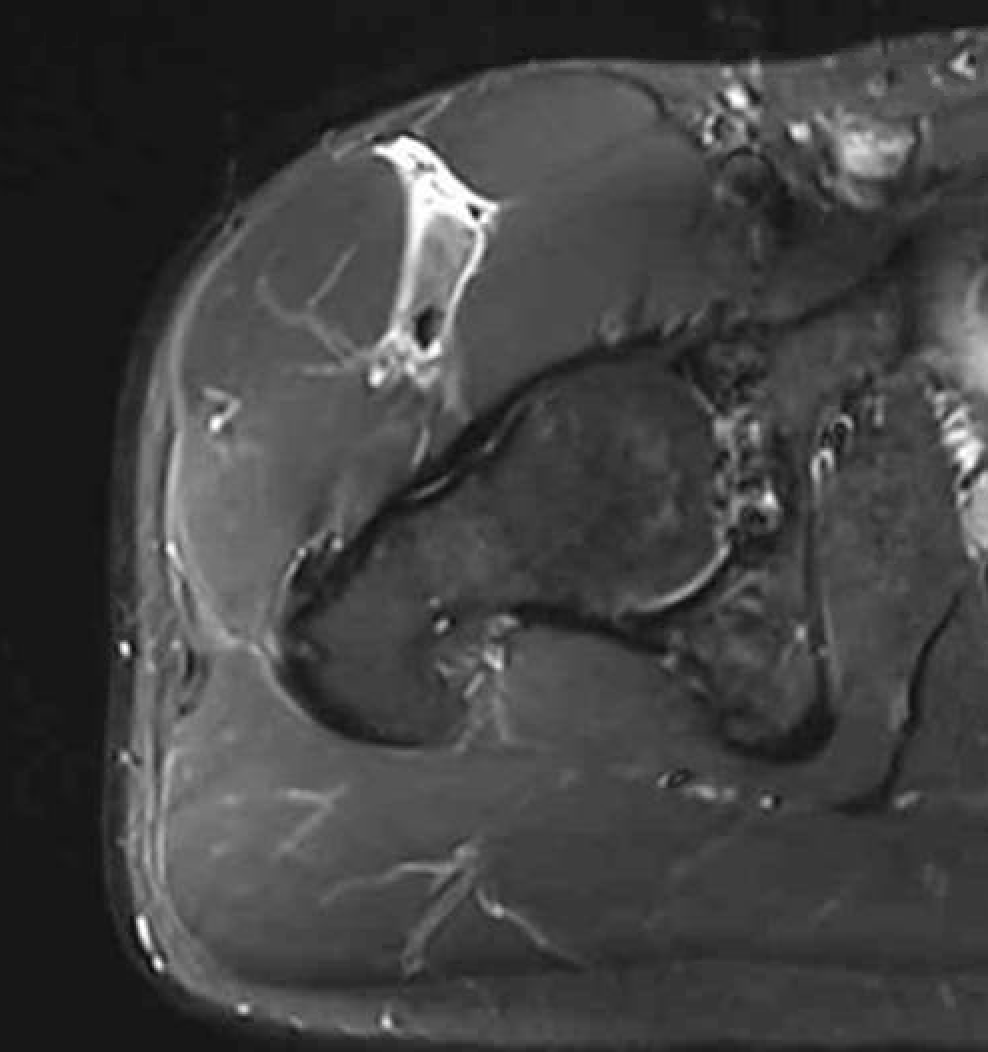

Grade 3C proximal central tendon rectus femoris

Grade 4C direct head MTPJ rectus femoris